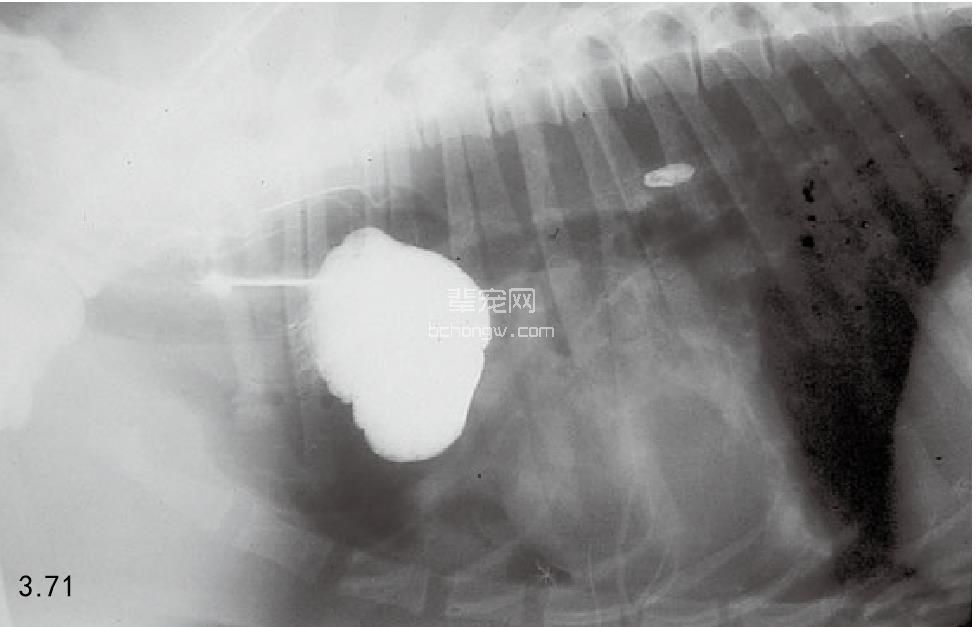

食管憩室 通过X线片、造影或内镜检查可以诊断(图3.71)。

图3.71 一只9岁杂种犬的食道憩室内充满了造影剂,该犬表现的症状为反流和口臭。